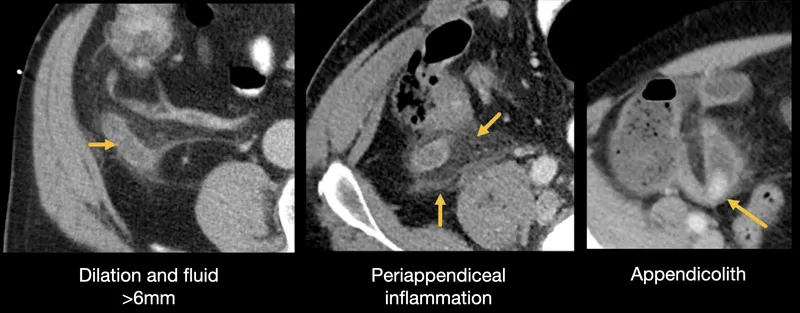

+ **Ultrasound first**: **85%** sensitive for cholecystitis, appendicitis

+ **CT if ultrasound negative**: **98%** sensitivity for most pathology